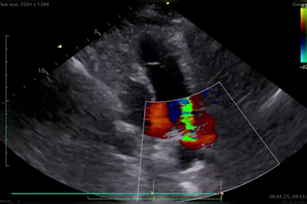

Фигуры